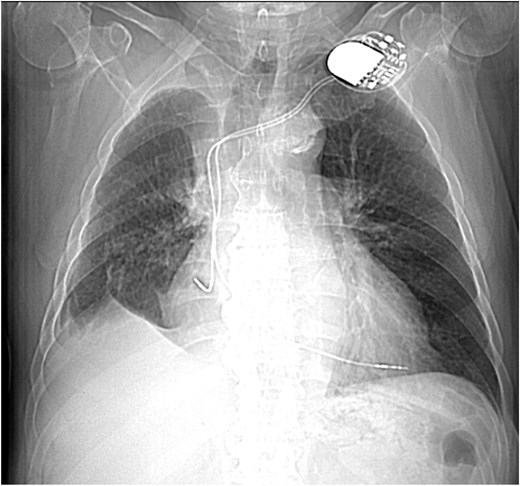

This 78-year-old man initially presented with a chest infection in October 2024, where a chest X-Ray (CXR) showed right upper lobe (RUL) consolidation accompanied by a pleural effusion (Fig. 1). He had no other symptoms, including haemoptysis, shortness of breath, fever, anorexia, or weight loss. A follow-up computed tomography (CT) chest 6 weeks later revealed a large endobronchial lesion in the right main bronchus, resulting in consolidation and partial collapse of the RUL (Figs 2 and 3). He went on to have a positron emission tomography (PET) scan (Fig. 4), CT head, bronchoscopy, and endobronchial ultrasound (EBUS). Imaging revealed a 3.8 cm lesion in the right upper lobe bronchus, which was mostly occluded. The biopsies showed evidence of a myoepithelial carcinoma, a rare pulmonary neoplasm.

CXR showing right upper lobe consolidation with a small right pleural effusion (dual lead pacemaker noted).

His relevant past medical history included asthma, transient ischaemic attack, atrial fibrillation with pulmonary vein ablation, AV node ablation, and permanent pacemaker insertion.

The imaging features of myoepithelial carcinoma of the lung are not well described in the literature. Routine imaging included chest X-ray, and CT scans were done in all the cases reviewed in the literature. On CXR, lesions typically appear as non-specific opacities or shadows. CT findings are more variable, ranging from smooth, well-circumscribed heterogeneous masses to solid spiculated or nodular lesions with irregular borders. This variability complicates preoperative differentiation from other bronchial neoplasms [4]. PET imaging may offer additional diagnostic insight. Rosen et al. [4] reported two cases with hypermetabolic activity (SUV 6.6), consistent with our case, which demonstrated an SUV of 13.8, suggesting high metabolic activity despite the tumour’s indolent histogenesis.